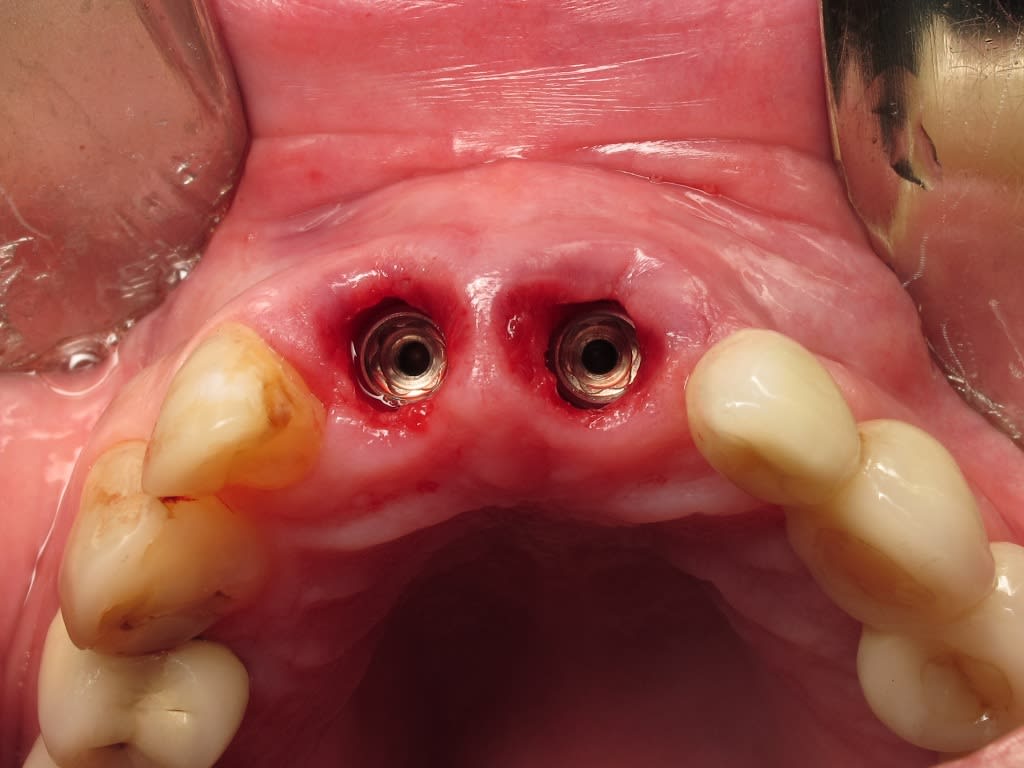

Accordingly, the patient enrolled in the multicenter study in December 2011. She opted for extraction, immediate provisionalization, and immediate loading, and visited both the oral surgeon (JMA) and prosthodontist (MAP) authors’ practices on the same day in January 2012 to consolidate these phases. Teeth Nos. 8 and 9 were extracted under local anesthesia (infiltration with lidocaine 2% with 1:100,000 epinephrine, 3.6 mL). The crowns were removed, then the roots were elevated and extracted. Osteotomy was made in type II (moderate) bone with Class A bone quality; all socket walls were intact. After tapping the sites, two 4.5-mm x 13-mm tapered implants (Genesis) were placed with primary stability of 40 Ncm (Figure 21) and 5-mm healing covers were placed (Figure 22 and Figure 23). The buccal socket gaps were grafted with spongious bone substitute (Bio-Oss®, Geistlich Pharma North America, www.geistlich-na.com). The gingival margins were reapproximated with 4-0 chromic sutures. Postoperative radiographs confirmed proper positioning in the alveolar bone.